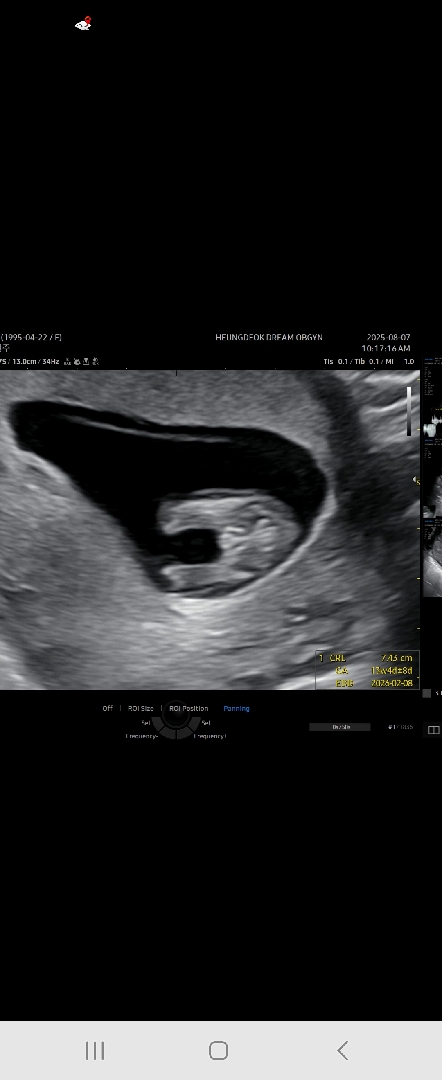

13주찬데 서브병원에서 초음파하다 요게보엿는뎅 아들일까요?,

삼지창 같은데 저건 딸이에요!